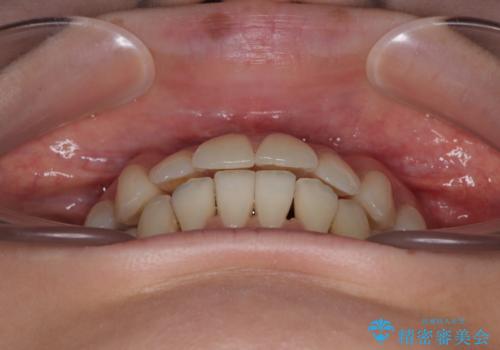

【モニター】前歯のデコボコをインビザラインで綺麗に

- 上下前歯のデコボコとクロスバイトを気にして来院された患者様です。

治療済みの処置歯が多いため、インビザラインを用いて矯正治療を行うこととしました。

下顎臼歯部にブリッジが装着されており、移動不可のため、IPR(歯と歯の間を削る)と歯列全体を拡大させることで、歯並びを整えていくこととしました。

インビザライン特有の奥歯の噛みにくさが治療後半に発現しましたが、無事に終了させることができました。